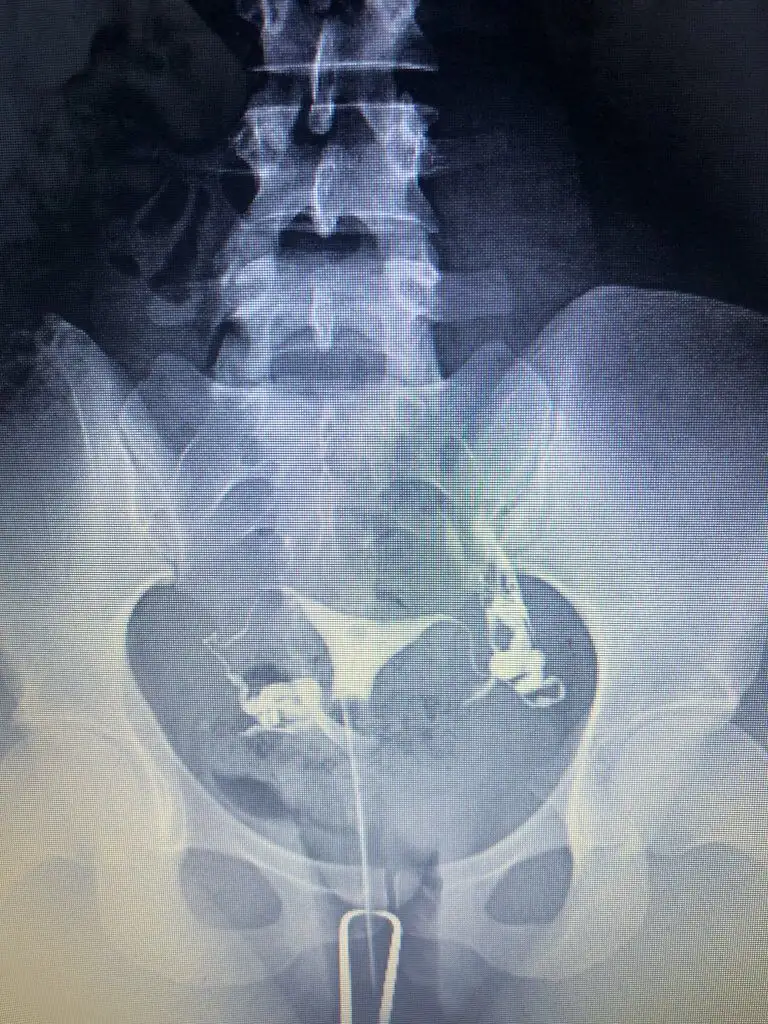

Cok teşekkür ederim.Nasil atabilirim bir bakayim cd de aldim görüntüyü yarin bilgisayardan atmayi deneyeyim bir. Kuşku birakan nedir nededi doktor.ben iki farkli doktora gittim ikiside ayni yorumu yapti. Sıvı dolu olan tüp bosaltilsa bile tekrarlama riski yüksek yani bu demek oluyor ki bosaltilr tüpü denedik bebek yapmayı olmadi herşey basa saracak tekrar hsg cekilecek kapandi mi diye gibi. Bu nedenle sıvı dolu tüpün alınması ortak karardi. Diğer tıkalı olan tüp ise hsg cekilirken doktorum zaten acmaya calismisti açılmamışti ameliyat sırasında da ilk oncelik onu açmaya calismak oldu ama geride bir dermoid kist (ameliyat sırasında görülebildi) tüpü tikamis ve acmays çalıştiklarinda tüpe basinc nedeniyle zarar vermis oyuzden oda alındı.İyi dileklerim sizinle

Özelden hsg görüntünüzü bana atar mısınız sakıncası yoksa ben iki kere çekildim normal raporlandı ama bir doktor aklımda kuşku bıraktıbu yüzden araştırma içine girdim, iki aşılamam negatif oldu

Ben Funda hanıma görselleri attığımda problem olduğunu düşünmüyorum dedi, ben çok fazla doktora gittim Çünkü bir neden bulunamıyordu yalnızca biri hidroselpenks dedi ve laparoskopi önerdi ben de o an çok şaşırıp çıktım. O yüzden bu durumu yaşayanlara mutlaka soruyorumCok teşekkür ederim.Nasil atabilirim bir bakayim cd de aldim görüntüyü yarin bilgisayardan atmayi deneyeyim bir. Kuşku birakan nedir nededi doktor.ben iki farkli doktora gittim ikiside ayni yorumu yapti. Sıvı dolu olan tüp bosaltilsa bile tekrarlama riski yüksek yani bu demek oluyor ki bosaltilr tüpü denedik bebek yapmayı olmadi herşey basa saracak tekrar hsg cekilecek kapandi mi diye gibi. Bu nedenle sıvı dolu tüpün alınması ortak karardi. Diğer tıkalı olan tüp ise hsg cekilirken doktorum zaten acmaya calismisti açılmamışti ameliyat sırasında da ilk oncelik onu açmaya calismak oldu ama geride bir dermoid kist (ameliyat sırasında görülebildi) tüpü tikamis ve acmays çalıştiklarinda tüpe basinc nedeniyle zarar vermis oyuzden oda alındı.

Benimkine hic benzemiyorBen Funda hanıma görselleri attığımda problem olduğunu düşünmüyorum dedi, ben çok fazla doktora gittim Çünkü bir neden bulunamıyordu yalnızca biri hidroselpenks dedi ve laparoskopi önerdi ben de o an çok şaşırıp çıktım. O yüzden bu durumu yaşayanlara mutlaka soruyorum

Ben İzmir’de değilim ama bir ayağım İzmir’de bu yüzden medikal aklımda olan bir yerdi buna istinaden kendisi ile yazıştım.Benimkine hic benzemiyorhidrosalpkinks diyen hangi doktor. Benim hsg cekimini yapan doktor Mehmet Bal ameliyatimida o yapti. Ama Funda hocaya hsg filmlerini göstermiş , Funda hanima o yolendirdi beni zaten. Ben bir de Engin Sarıca' ya gittim hsg raporumu götürdüm inceledi oda ayni yorumda bulundu

Yani acikcasi benimkini hatırladığım kadariyla ve simdi google dan baktığım diger örnek hidrosalpkinksler gibi degil görüntün yani bende boyle şiş bir yer gorunuyordu resmen. Hsg cekilirken ağrın oluyor mu ? Mesel ben tupleri acik olanlarda cok agrisi oluyor diye duymadim. Ben agridan mahvolmuştm ki anestezili cekilmeme rağmen. Bence normal gibi görünüyor tüplerin ama güvendiğin bir doktor varsa ve sartlaro cekimi iyi olan bir yer agrinda olmuyorsa için rahat etsin diye tekrar cektirebilirsin. Ama bence hic gerek yok bir kaç doktor ayni yorumu yaptiysa eğerBen İzmir’de değilim ama bir ayağım İzmir’de bu yüzden medikal aklımda olan bir yerdi buna istinaden kendisi ile yazıştım.